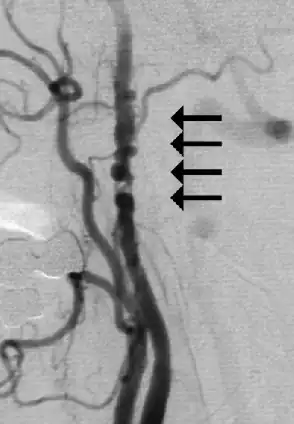

| Angiogram showing narrowing of the arteries in the neck in a women with a TIA[1] | |